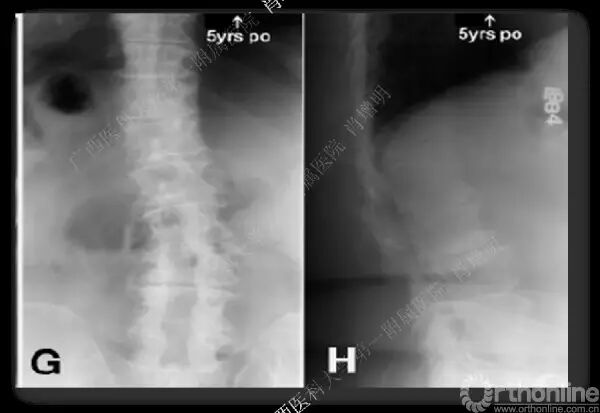

退变性脊柱侧凸是由于椎间盘退变后继发小关节退变,椎管和神经根管容积变化以及脊柱失稳,畸形等病理改变,以疼痛和神经压迫症状为主要表现的常见疾病。

退变性脊柱侧凸多发于50岁以上的中老年群体,是现代常见的老年疾病。多年来,针对该病的临床研究一直没有停步,广西医科大学第一附属医院肖增明教授细致地介绍了该病的诊疗进展。